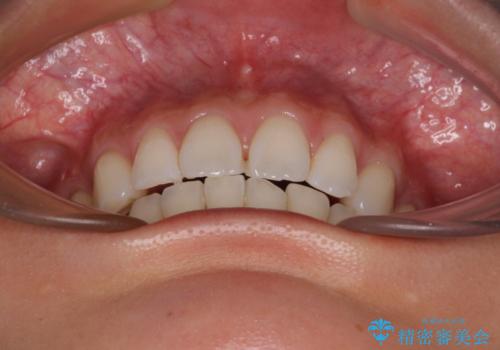

- 飛び出した前歯を気にして来院された患者様です。

口元を引っ込めるために上下左右の第一小臼歯4本を抜歯することとしました。

結婚式を行う予定があるとのことで、表側のワイヤー装置で、速やかに治療を終えられるようにしました。

途中妊娠と出産がありましたが、予定よりも早く治療を終えることができました。